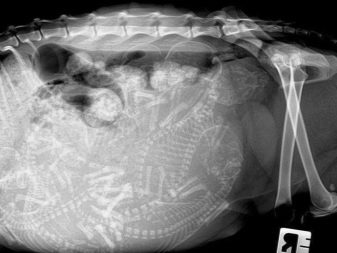

A ramp cat can give birth to no more than 4 kittens, if an ultrasound shows 6 individuals, then a cesarean section will be required, otherwise the cat will die in childbirth.